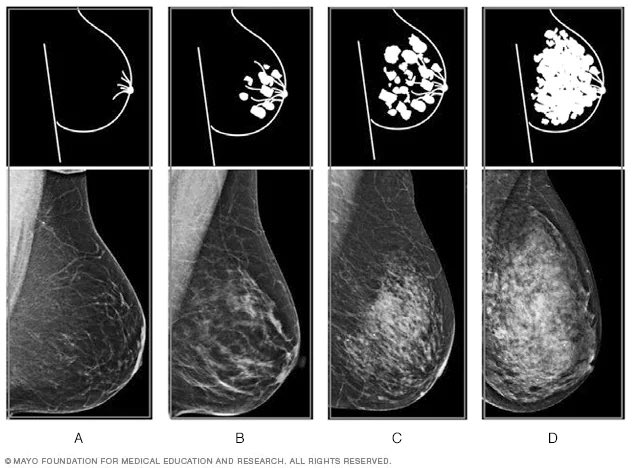

حساسيةالكشف عن التغيرات في الثدي عاليه بهذا الفحص عند أغلب السيدات الا في حالات نوعية الثدي الكثيف الانسجة، الصورة تظهر اختلاف كثافة انسجة الثدي لدى النساء والتي قد تؤثر على دقة قراءة الاشعه اذا كانت عالية(اللون الابيض هو نسيج الثدي)، وهنا يتم اجراء فحص مكمل وهو الاشعه الصوتيه3️⃣